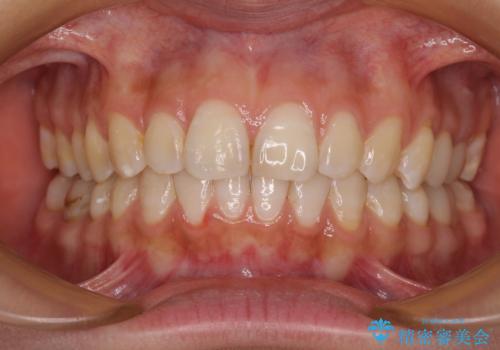

【モニター】隠れている下顎の前歯をインビザラインで改善

咬み合わせと目立っていた銀歯が改善され、患者様には大変満足していただきました。